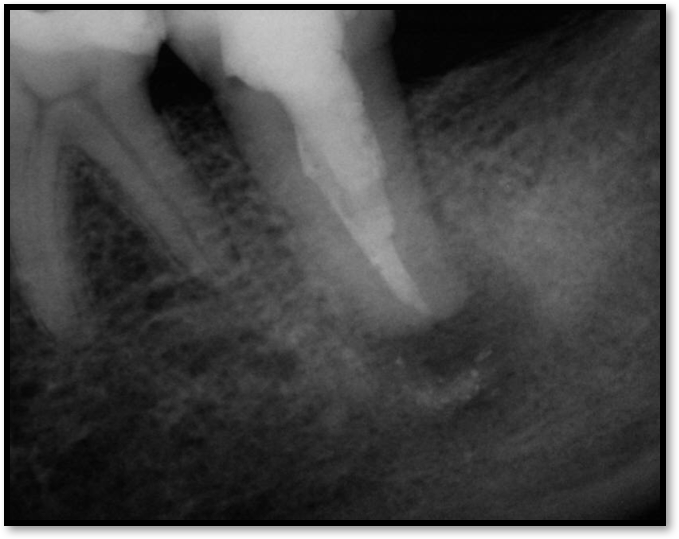

Root-Canal Access

Ultimately, the aim in endodontics is to preserve the tooth as long as possible for the patient. A clinician may want to do a root canal but must face realistic concerns, such as not having enough tooth.Figure 1 shows a case where the clinician was able to access four canals through a zirconium crown, with limited access. Generally, it is preferable to err on the side of opening larger and cleaning out well. If the access is too small, three problems arise: (1) clinicians may not clean effectively; (2) there is a greater chance of separation because there is not enough of a straight path, and (3) canals may be missed. Conversely, if clinicians open too large, they can destroy the tooth. There is a happy medium where the result is fine-tuned and engineered perfectly. Although the perfect result is not always possible or ideal, clinicians continue to strive for it. The best approach is to find the canals and then open them up under a microscope to get enough access. This gives the clinician whatever shape is needed for conservative access.

Fig 1. Limited access.

Figure 1